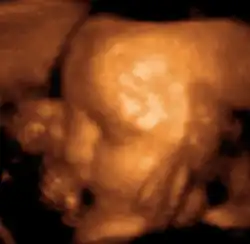

Ультразвуковое исследование используется для изучения внутренних половых органов женщины, состояния беременной матки, анатомии и мониторинга внутриутробного развития плода.

Трёхмерное ультразвуковое исследование 29-недельного плода.

Этот эффект широко применяется в акушерстве, так как звуки, идущие от матки, легко регистрируются. На ранней стадии беременности звук проходит через мочевой пузырь. Когда матка наполняется жидкостью, она сама начинает проводить звук. Положение плаценты определяется по звукам протекающей через неё крови, а через 9 — 10 недель с момента образования плода прослушивается биение его сердца. С помощью ультразвукового исследования можно также определять количество зародышей или констатировать смерть плода.

Уже с третьей недели от момента зачатия можно увидеть эхонегативное образование плодного яйца диаметром 5—6 мм в полости матки. С 4—5 недель возможна визуализация эмбриона в виде эхопозитивной полоски размером 6—7 мм. Головка эмбриона становится видимой как отдельное анатомическое образование средним диаметром 10—11 мм на 8—9 неделе[8].